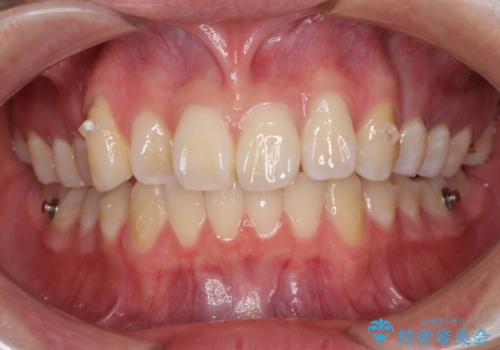

- 八重歯を気にして来院された高校生の患者様です。

ボディーコンタクトの激しい部活動を行っているため、補助装置とインビザラインを用いて、部活動を継続しながら治療を行うこととしました。

八重歯を効率よく改善するため、補助装置を使用して上顎の奥歯を後方に移動させました。

部活動をしながらでしたが、マウスピースをしっかりと装着してくださったので、1年半程度で終了することができました。